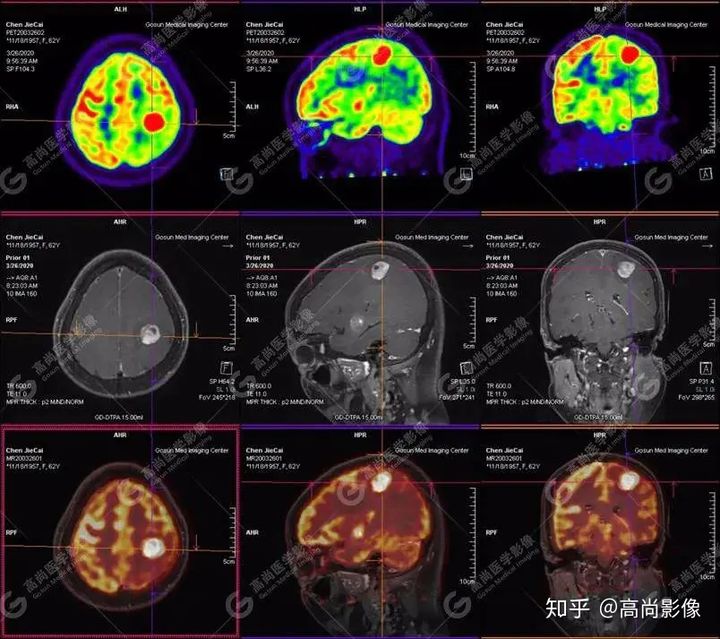

【高尚醫(yī)療影像】【多模態(tài)影像】顱內(nèi)淋巴瘤PET-MR融合顯像1例

【病史摘要】患者,女,62歲

失眠伴記憶力減退近一月入院檢查,無(wú)頭痛、嘔吐、四肢活動(dòng)正常

外院CT提示,顱內(nèi)多發(fā)占位,轉(zhuǎn)移瘤可能

左側(cè)顳葉、頂葉、左側(cè)基底節(jié)區(qū)及胼胝體部多發(fā)結(jié)節(jié)狀高代謝病灶,部分合并囊變、出血,MR平掃+增強(qiáng)示不均勻輕、中度強(qiáng)化,綜合考慮為顱內(nèi)原發(fā)惡性腫瘤,以淋巴瘤可能性大

【病理結(jié)果】彌漫大B細(xì)胞淋巴瘤

淋巴瘤病變多位于中線兩旁的深部腦實(shí)質(zhì)、側(cè)腦室周圍及腦表面,甚少累及腦膜和顱骨,幕上多于幕下,呈分葉狀或握拳狀,水腫及占位效應(yīng)較輕,部分病灶內(nèi)可見(jiàn)囊變、出血及其邊緣的硬環(huán)征、尖角征、臍凹征,增強(qiáng)掃描呈現(xiàn)的“臍凹征或者“握拳征”是淋巴瘤較為特征性的一個(gè)表現(xiàn)。

18F-FDG PET PET顯像中呈明顯高代謝病灶。